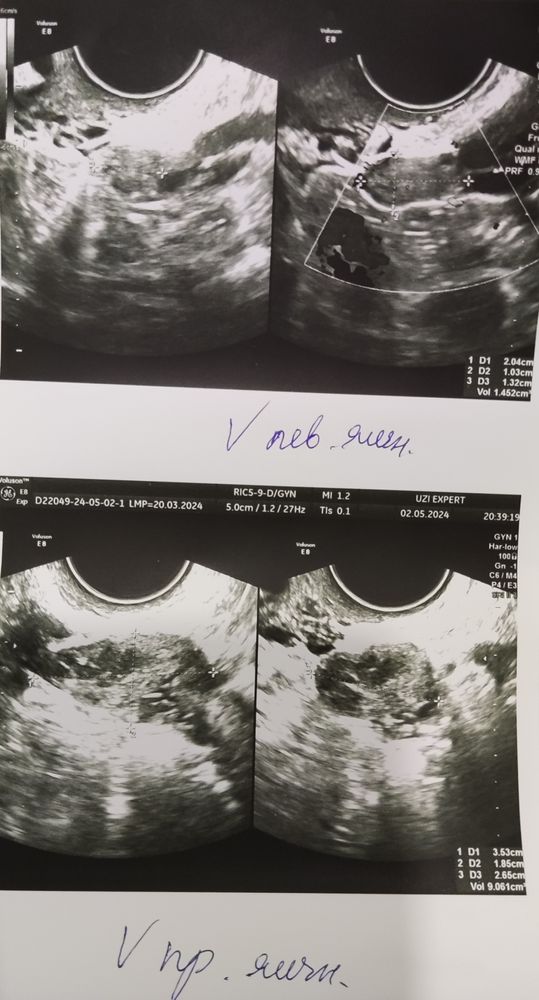

Сделала УЗИ

Добрый день. Ну аденомиоз, это эндометриоз. Он есть. А по УЗИ и анализам полная несостыковка. На 7 день цикла странно что есть жёлтое тело, скорее всего оно от прошлого цикла. НО при ФСГ 37 по идее не может быть там ни желтого тела, ни фолликула доминантного. Тут по любому ошибка или что то другое. На 7 день при такой дисфункции вообще всё мало информативно. Надо сделать в следующем цикле, если он в ближайшее время будет с ФСГ 37, всё повторить на 3-4 день цикла и не позже. И понять что это за образование в яичнике, уйдет отлично, не уйдёт,надо разбираться... По мне с ФСГ 37 это и не фолликул и не жёлтое тело.

ната, вообще конечно, врачи называются...добавила фото УЗИ яичников. Искала похожее фото у кого нибудь жт с прошлого цикла, ничего не нашла. Чтоб хоть сравнить что это такое.

Виктория, ну если это дф значит надо пробовать)) я у нее спросила может это киста!? Она нет, это жт с прошлого цикла🤷

Виктория, сейчас почитала ДФ на 7 дц как-то много 17 мм. Я постоянно хожу в эту клинику на УЗИ, могла ли она перепутать? ДМ с ЖТ в регрессии.

У вас оба по УЗИ работают

Екатерина, ну про левый сказали что он уменьшается, у меня там трубы нет. На него не надеюсь. Хотя когда были обе трубы, овуляция была справа, а внематочная слева ((

30 ДЦ. В ожидании чего-то) Длинные циклы, СПКЯ. ЖТ или ДФ ???